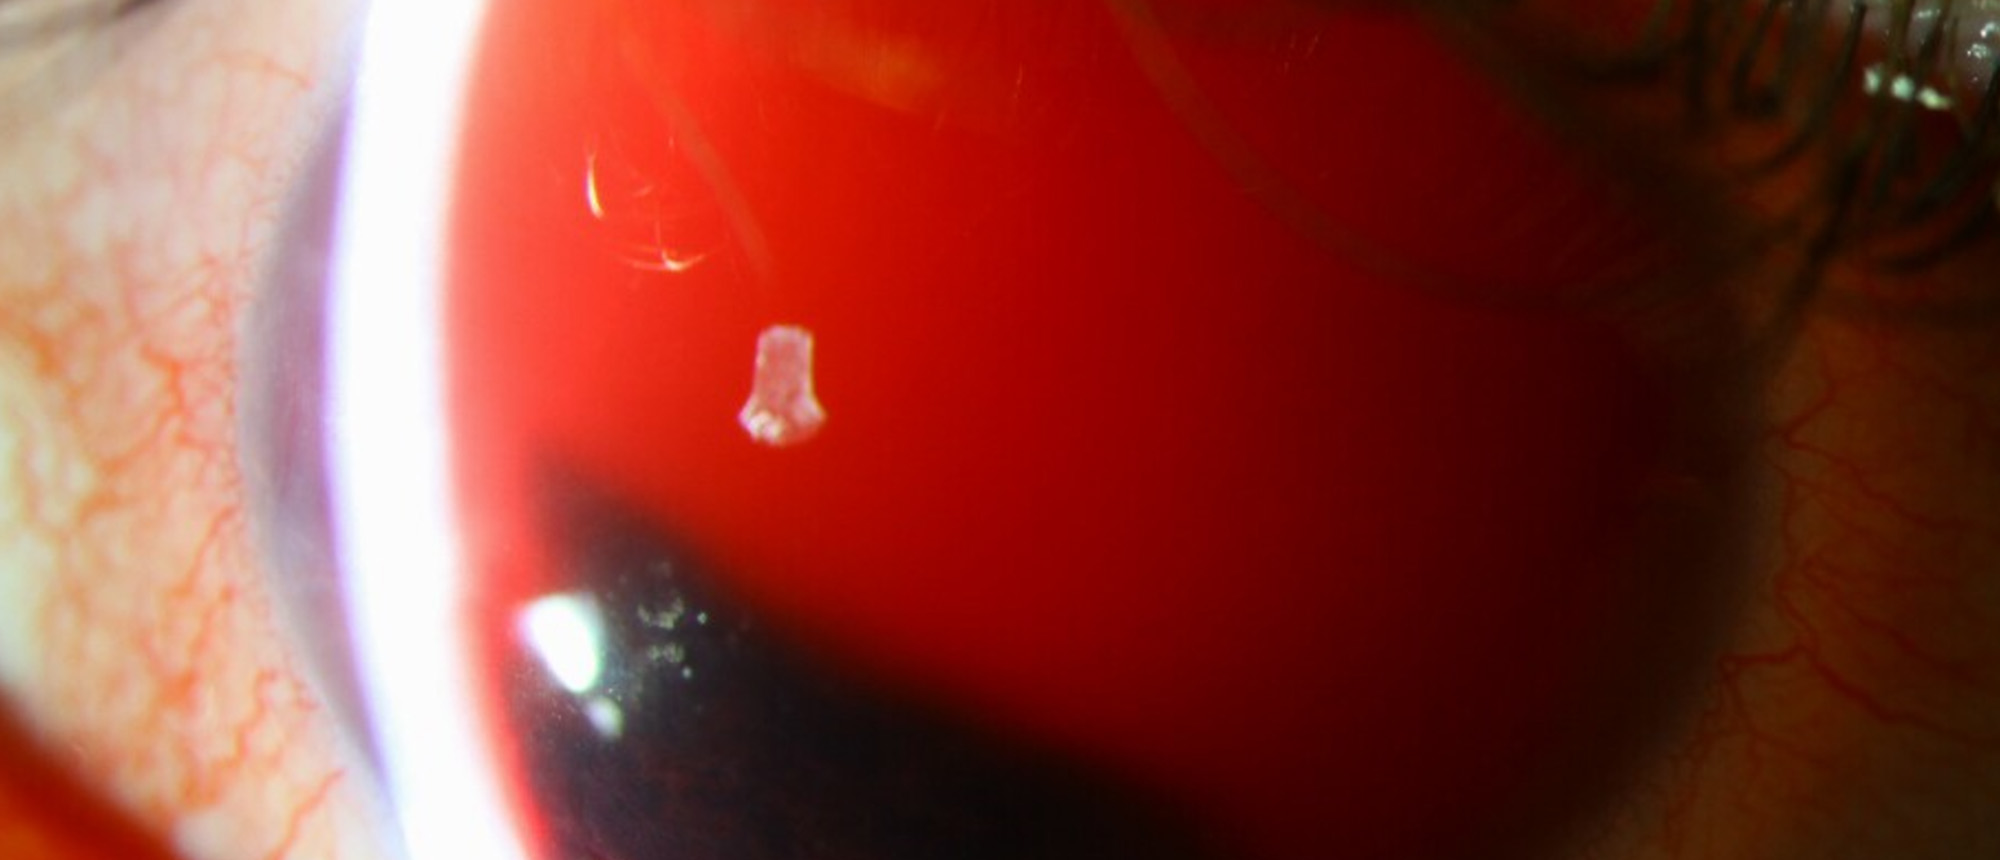

Pseudophakic Bullous Keratopathy with Prior Descemet Membrane Tears due to Forceps Trauma

Abstract A patient with a history of forceps trauma at birth and amblyopia of the left eye who presents with persistent corneal edema 1 year after uncomplicated cataract surgery. Initial visual acuity was 20/200, intraocular pressure was 10, and pachymetry was 698 um. On clinical examination there …